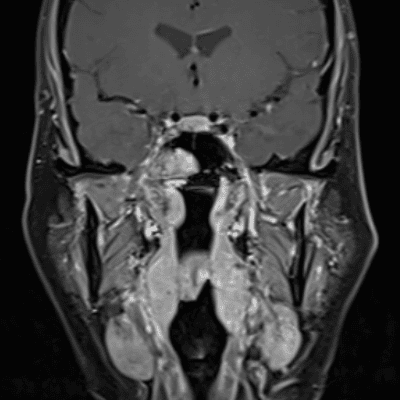

Classic Cases